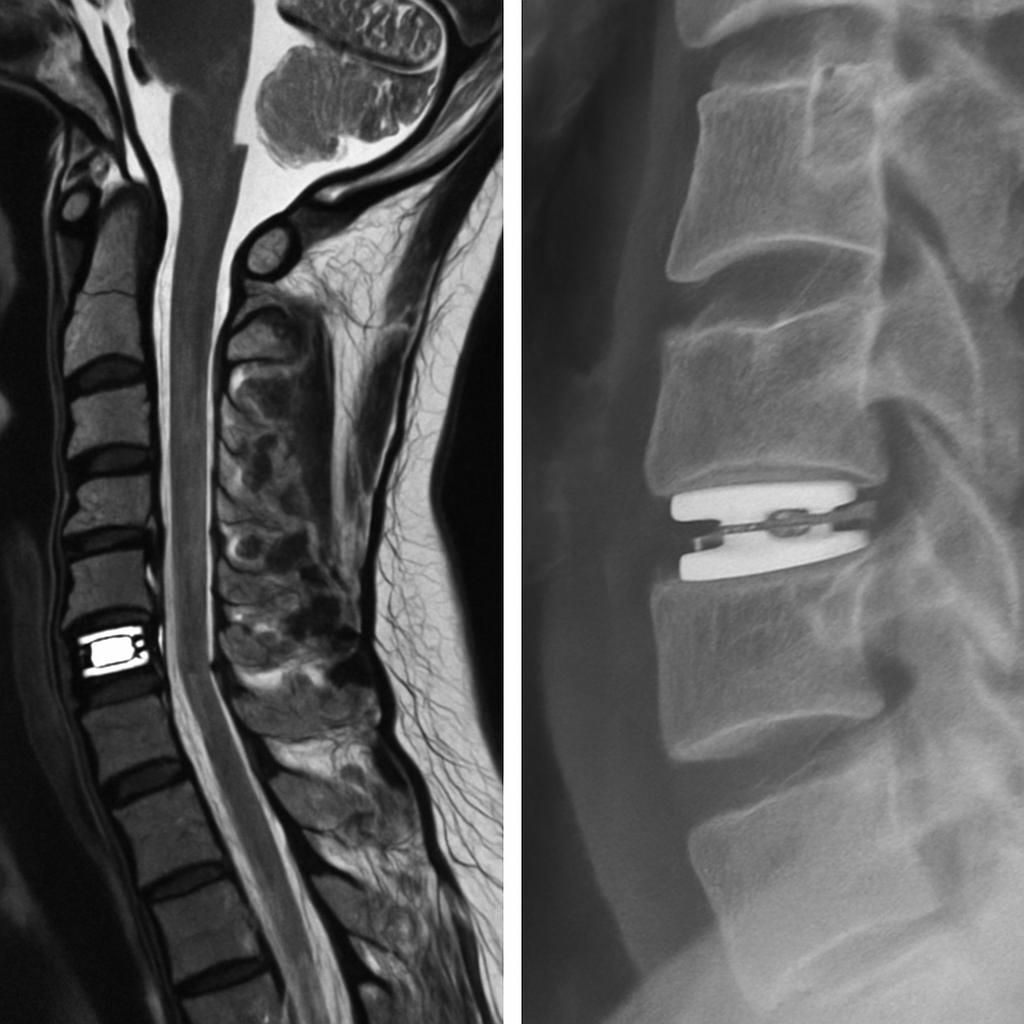

Un suivi régulier avec le chirurgien ou l’expert en implants vertébraux permet une évaluation clinique approfondie et un ajustement du parcours de soins. Certaines consultations utiliseront des outils d’imagerie médicale avancée, tels que l’IRM ou la tomodensitométrie, avec ou sans reconstructions 3D, pour contrôler la position de la prothèse discale et exclure toute complication mécanique. Cette surveillance objective renforce la confiance des patients dans leur processus de récupération.

| IRM cervicale | Évaluation des tissus mous, détection des complications neurologiques | Selon symptômes ou suspicion clinique |